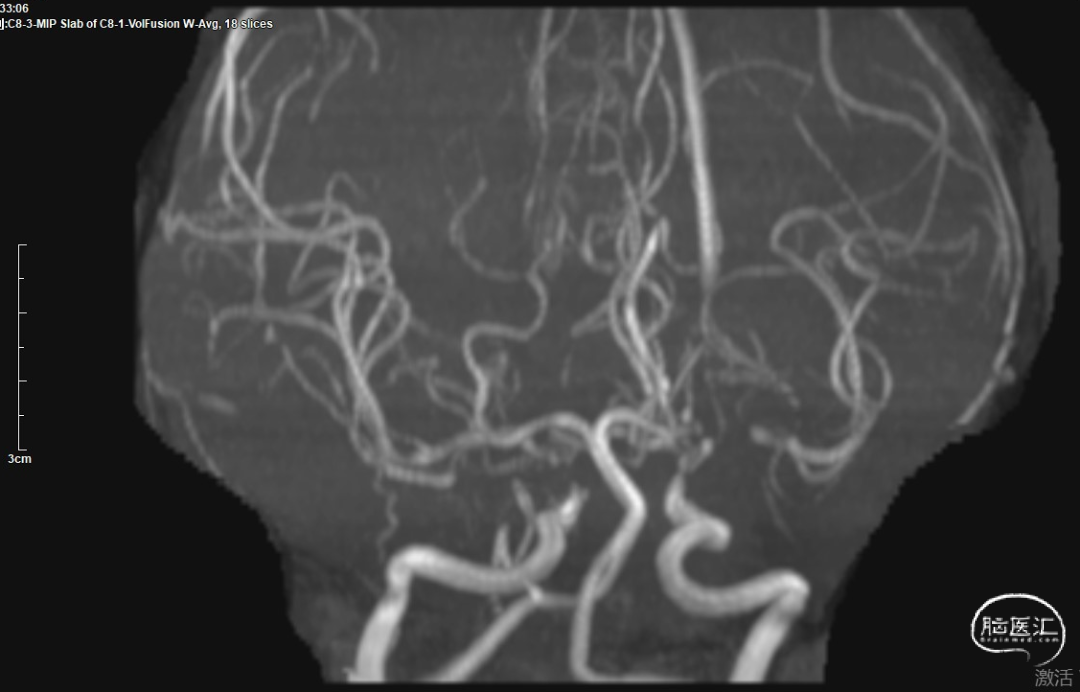

颅脑MRA检查示:双侧颈内动脉海绵窦段、交通段狭窄,双侧大脑中动脉水平段狭窄。

➢ 脑血管造影

拟全麻下行脑血管造影+择期血管内治疗。脑血管造影评估后,直接处理责任病灶。